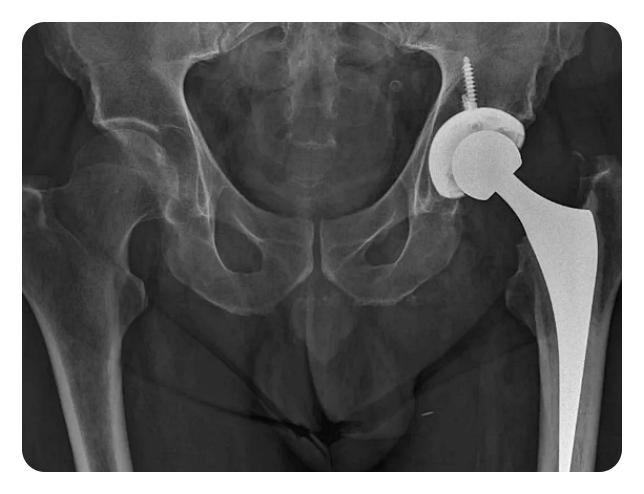

인공관절 치환술: 이 수술은 고관절이 심각하게 손상되거나 통증으로 인해 일상 생활에 지장을 주는 경우에 시행됩니다. 이 수술은 손상된 관절을 제거하고 인공 관절로 대체함으로써 이루어집니다.

고관절 인공관절 수술은 손상된 부위를 대체하고 통증을 완화하는 데에 효과적입니다. 또한 환자의 개인적인 상황에 맞춰 맞춤형 수술이 가능하며, 통증 완화와 관절 기능 개선을 통해 삶의 질을 향상시킵니다. 이러한 수술은 장기적인 효과를 가지며, 환자들에게 삶의 활동성을 되찾을 수 있는 기회를 제공합니다.

영상 진단 검사는 X-ray, MRI, CT 등을 통해 고관절의 상태를 확인하고, 수술 계획을 세웁니다.